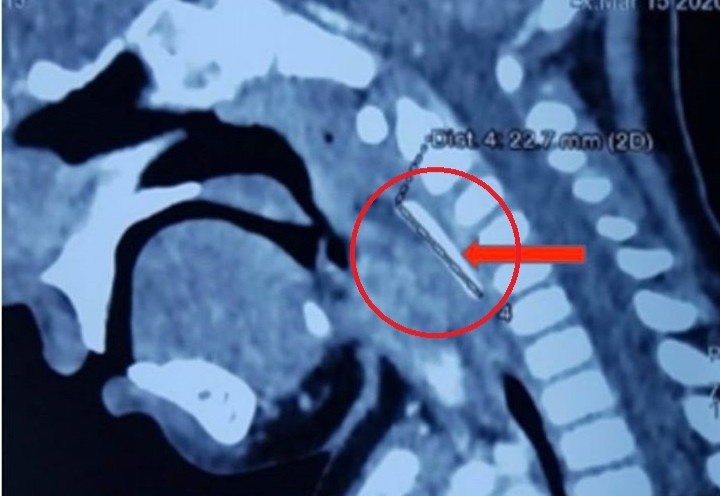

Ngày 30/7, Bệnh viện Quân Y 175 (Bộ Quốc phòng) cho biết đơn vị này vừa kích hoạt hệ thống Code Red, cấp cứu kịp thời nam bệnh nhân L.T. (25 tuổi, ngụ quận Gò Vấp, TP.HCM) nguy kịch tính mạng do đa chấn thương. Trước đó, do bẩt cẩn, bệnh nhân bị ngã từ tầng 2 xuống hàng rào cổng và bị các thanh sắt đâm thấu bụng.

Tại bệnh viện, ê-kíp mổ cấp cứu gồm các bác sĩ khoa Ngoại bụng kết hợp khoa Ngoại lồng ngực - Tim mạch, nhanh chóng xử lý đưa dị vật ra ngoài. Sau khi mở ổ bụng, bác sĩ ghi nhận dị vật là hàng rào sắt đâm xuyên các mạch máu và tĩnh mạch treo tràng trên, thủng tá tràng, rách tĩnh mạch chủ bụng…

Bệnh nhân được khâu các vị trí tĩnh mạch bị thủng, kẹp cầm máu, đặt sonde dạ dày, rửa và lau sạch ổ bụng. Sau khoảng 8 giờ, ca mổ kết thúc. Bệnh nhân được chuyển về khoa Hồi sức tích cực để tiếp tục theo dõi.